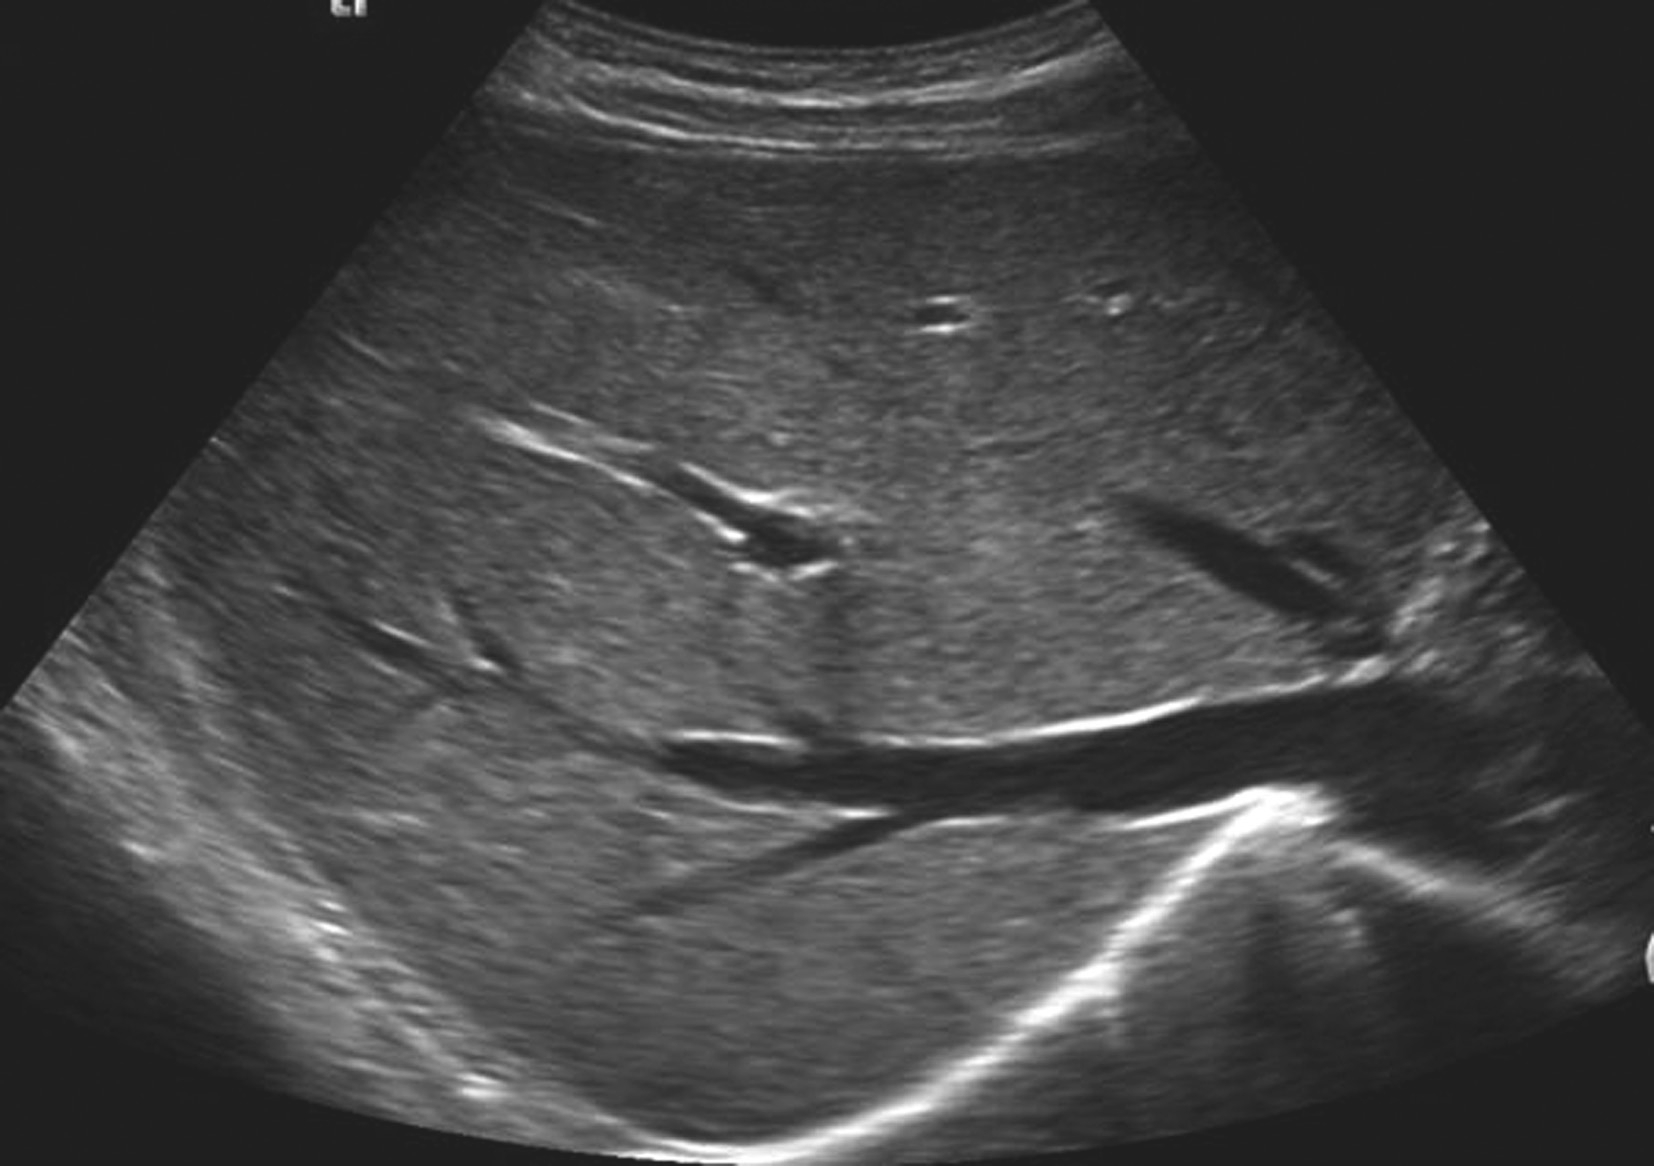

【声像图表现】

局限性脂肪肝超声像图表现如图5-21-4所示:

图5-21-4 局限性脂肪肝二维灰阶图像

(1)灰阶超声:

也称为叶段型脂肪肝,肝实质脂肪变分布在某一肝叶或肝段,或呈斑片状或结节状,回声明显增强,境界清晰,无占位效应,肝内管道结构正常。

(2)彩色多普勒超声:

脂肪变的肝叶或段内血管无受压及推移,血流可正常显示。

(3)超声造影表现:

局灶性脂肪变性结节样异常区在动脉相、门脉相及延迟相与正常肝组织增强表现一致,未见异常灌注区,结节样回声消失。